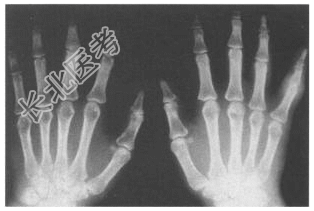

- [材料题] 患者,女,52岁。双手晨僵感一年余,关节肿胀3个月余。双手X线平片见下图,类风湿因子阳性,抗“O”轻度增高,血沉为25mm/h。

- 简答题1、该病最可能的诊断是?

- 简答题2、类风湿关节炎的典型症状和诊断方法是什么?